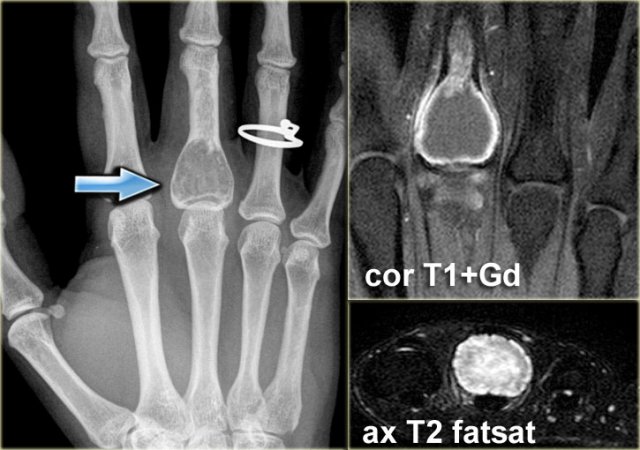

Chondromyxoid fibroma (3)

On the left a well-defined lytic lesion at the base of the 2nd metatarsal bone.

There is no mineralisation.

T1-weighted images before and after Gd-DTPA demonstrate some expansion and lobulation.

On the T1-weighted image before contrast there is a nonspecific intermediate signal intensity.

After the administration of Gadolinium there is thick peripheral enhancement.

Differential diagnosis based on plain radiograph: giant cell tumor or chondroid lesion, i.e. enchondroma, low grade chondrosarcoma or CMF.

Biopsy revealed CMF.

Although this is a rare lesion, the foot is one of the preferential sites of origin.